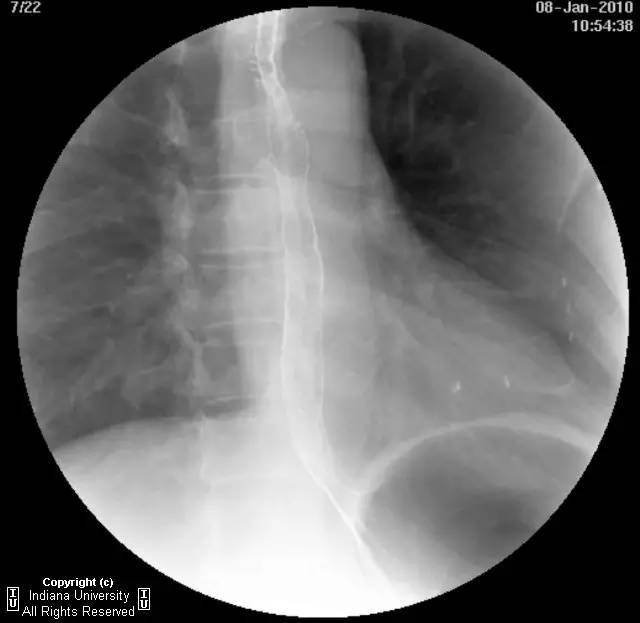

【影像学表现】下咽部正常,环咽肌功能正常。颈段食管无外生性病变压迫或异常扩张。胸中段食管长节段狭窄,逐渐移行为正常食管粘膜。大量小的烧饼样钡斑位于相应食管外呈浮萍样,与食管管腔无直接交通。稠或稀钡剂通过均无延迟。1cm钡剂片延迟通过,约30分钟后自动溶解。余食管动力正常。

【诊断】食管壁内假性憩室并长节段狭窄

Long segmentstricture with esophageal intramural pseudodiverticulosis